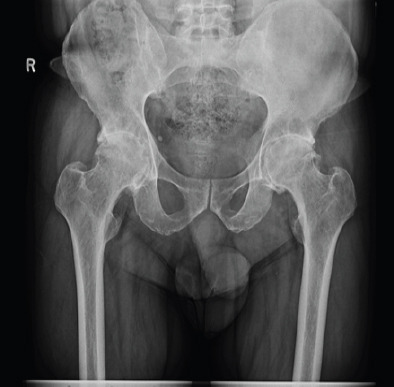

Case report: This case study relates the history of a 56-year-old man with ankylosing spondylitis who underwent bilateral THA using a CoC articulations. Initially asymptomatic for 4 years, he developed pain, swelling around the right hip, and his imaging showed extensive osteolysis with pseudotumor formation. His fine-needle aspiration cytology report was inconclusive, so he underwent stage 1 procedure that is removal of prosthesis and biopsy. His histopathology report confirmed pseudotumor formation with presence of fibrin, proliferating fibroblasts, hemosiderin-laden macrophages and lymphocytes. Since the patient was not keen on second stage revision arthroplasty, he was mobilized with heel and sole raise and walking aid.

Conclusion: Pseudotumor formation occurred without any damage to ceramic head and liner, without any malposition of components, with no impingement between components and normal metal ion levels in our case. This case report further strengthen existing literature about pseudotumor formation in CoC articulation. Further studies needed to know exact tribology and individual immune response for ceramic wear debris.